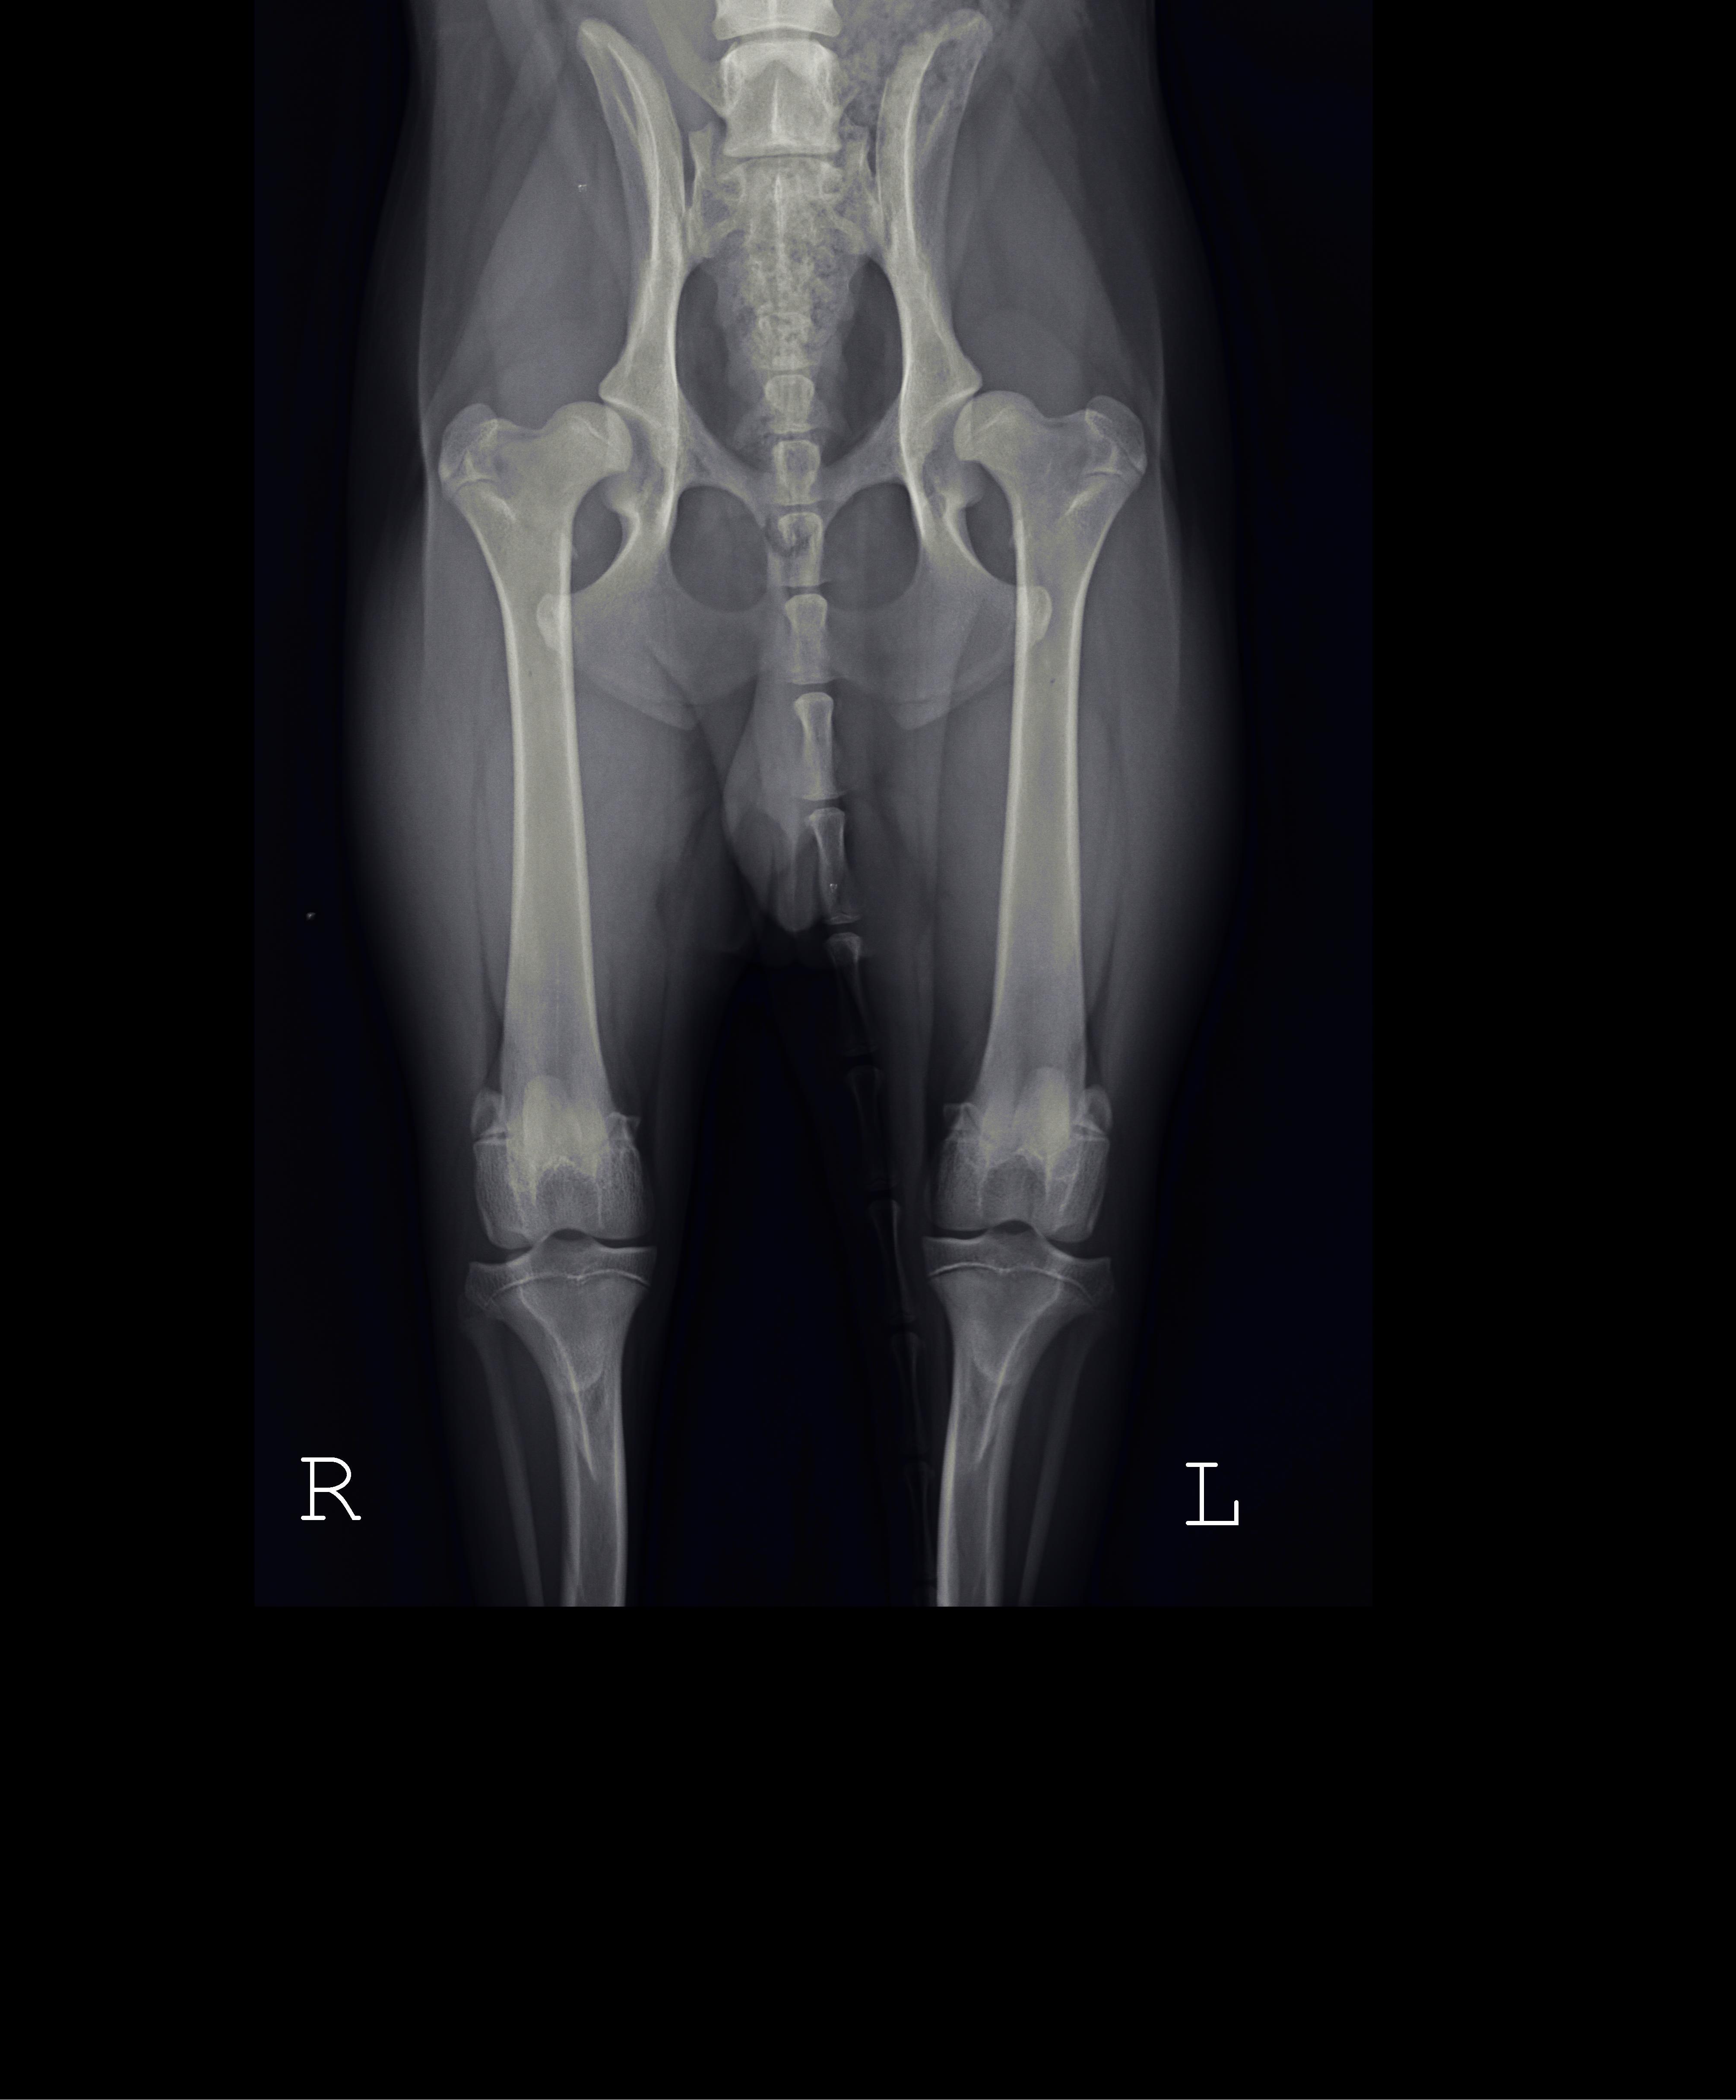

Na forum chciałbym się podzielić naszą historią. Od maja jestem posiadaczem border collie, którego wg. zapewnień hodowcy rodzice są wolni od dysplazji. Niestety w wieku ok. 7 msc zauważyliśmy, że  jest problem z chodzeniem, widać taki zajęczę skoki tylnych łapek. Udaliśmy się do kliniki w Poznaniu gdzie lekarz na pierwszy rzut oka stwierdził dysplazję, niestety potwierdziliśmy to badaniem RTG (załączam zdjęcia). Okazało się, że jest to już ciężka dysplazja typu D. Po początkowym szoku chcieliśmy działać żeby jakoś to naprawić. Weterynarz, który wykonał RTG zaproponował metodę resekcji obu głowek- terapia dosyć drastyczna i nieodwracalna(koszt ok. 1700zł za jedną nogę). Stwierdziliśmy, że poszukamy informacji i pomocy u innych lekarzy. Dwóch z trzech stwierdziło, że resekcja to zły pomysł a pies będzie po niej inwalidą. Jeden z weterynarzy polecił wg. niego najlepszą w Europie klinikę w Czechach ABvet, ok. 400km od nas ale czego się nie robi dla kochanego pupila. Po kontakcie mailowym (zero problemów z językiem) i przesłaniu RTG umówiliśmy się na wizytę. Na miejscu lekarz stwierdził, że pies ma tragiczne biodra, ale na szczęście dla niego w wieku 8 msc można jeszcze zrobić podwójną osteotomię obu stawów. Na informację co zaproponowali inni lekarze tj. resekcję powiedział, że nigdy w życiu nie zrobiłby tego takiemu młodemu psu i dla niego byłoby to inwalidztwo. Dodatkowym atutem za osteotomią jest to, że nie jest bardzo wyrośnięty i waży 16kg. Lekarz powiedział, że mamy 2 dni na zastanowienie bo w tym przypadku każdy dzień się liczy. Koszt operacji oszacował na 3tys za jedną nogę. Stwierdziliśmy, że jak się wzięło psa to trzeba też wziąć za to odpowiedzialność i dać mu bezbolesne życie. Doktor powiedział, że nie ma terminów na msc. do przodu, jednak ten niecierpiący zwłoki przypadek gdzieś "wciśnie". Po tygodniu miała mieć miejsce pierwsza operacja tj. 4 grudnia 2018r. Pieska zawieźliśmy na 8 rano, zostawiliśmy go w klinice, poinformowano nas, że pies po operacji zostanie jeszcze ok 2-3 dni. Niestety z przyczyn technicznych operacja przesunęła się o jeden dzień. 7 grudnia dostaliśmy informację, że piesek jest gotowy do odbioru. Lekarz przekazał nam dobre wiadomości, że wszystko się udało a następna operacja będzie 20 grudnia. Ciąg dalszy nastąpi.

Cywil jest po drugiej operacji, stan biodra był tragiczny, jednak udało się poprawić panewkę i jej kątowanie. Pierwsza rana się zagoiła bardzo szybko. Z drugą jest trochę komplikacji, ponieważ zaczął się zbierać płyn i trzeba było go spuścić. Pies dochodzi do siebie i zaczyna coraz bardziej obciążać lewą nogę.

Zdjęcie RTG po dwóch operacjach: https://zapodaj.net/50ff53cd830e2.jpg.html